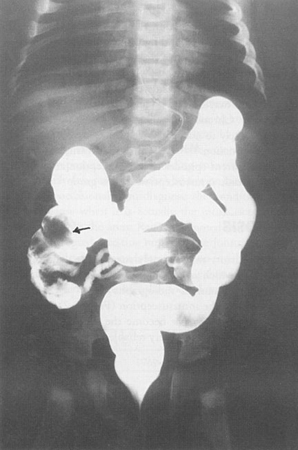

Enema com contraste revelando intussuscepção ileocólica (seta preta)

Do acervo de Dr. KuoJen Tsao; usado com permissão